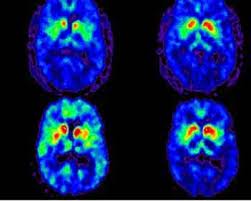

La Docteure Viviane Tabar, présidente du département de neurochirurgie au Memorial Sloan Kettering Cancer Center et cofondatrice de BlueRock, explique : « L'objectif est de positionner ces cellules précisément là où elles peuvent établir des connexions fonctionnelles avec d'autres neurones ». Les résultats sont remarquables : amélioration des symptômes moteurs de 50 % après 18 mois ; production effective de dopamine confirmée par imagerie TEP ; amélioration significative du sommeil et de la mobilité quotidienne ; gain de jusqu'à 20 points sur l'échelle UPDRS pour les patients ayant reçu la dose maximale.